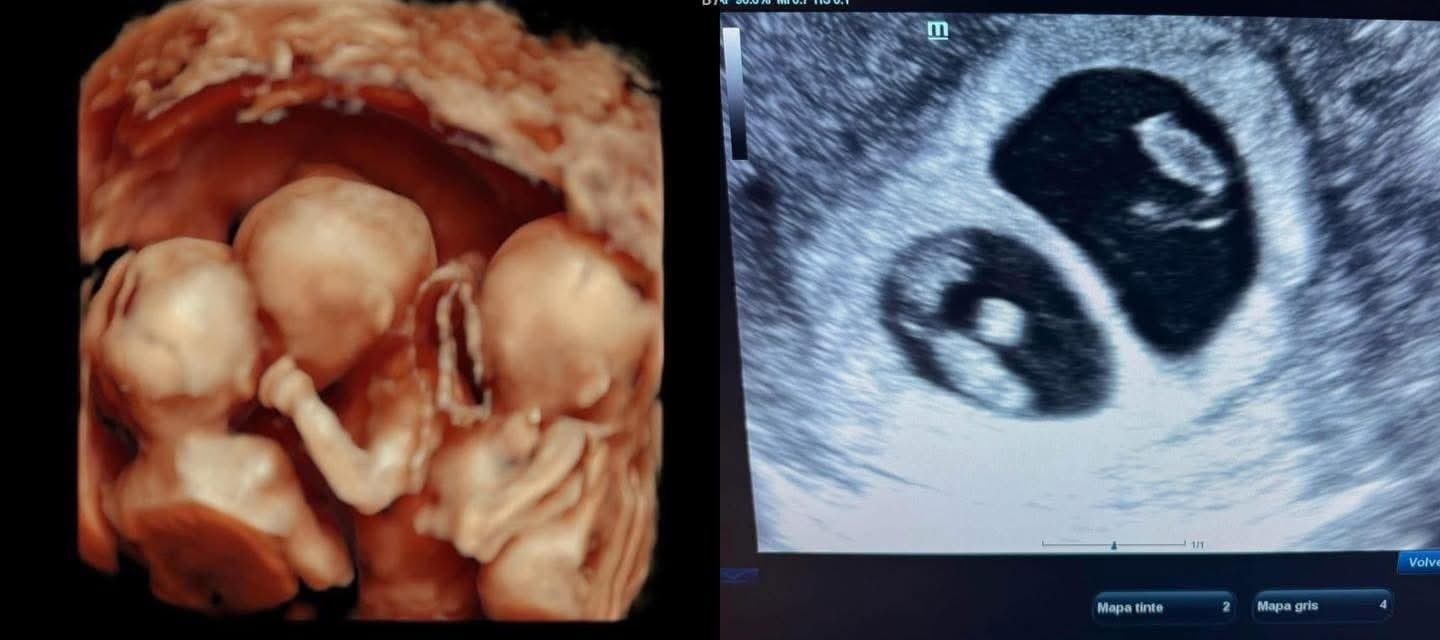

Reynosa presencia nacimiento de trillizos y el adiós de un pequeñero guerrero.

El 26 de mayo de 2025, Evelin Yanitze, de 27 años, dio a luz a trillizos prematuros mediante cesárea en el Hospital Materno Infantil de Reynosa, el tercer caso en la historia del hospital. El embarazo fue atendido por el Dr. Bernal Ginecólogo Privado de OBGYN Reynosa, logrando u ...